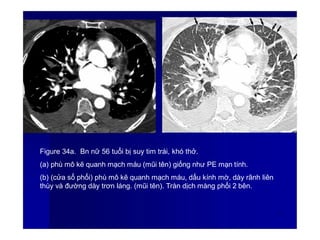

Figure 34a. Bn nữ 56 tuổi bị suy tim trái, khó thở.

(a) phù mô kẽ quanh mạch máu (mũi tên) giống như PE mạn tính.

(b) (cửa sổ phổi) phù mô kẽ quanh mạch máu, dấu kính mờ, dày rãnh liên

thùy và đường dày trơn láng. (mũi tên). Tràn dịch màng phổi 2 bên.

4

7